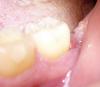

ElenaAl Опубликовано 19 мая, 2011 Автор Поделиться Опубликовано 19 мая, 2011 Дорогие стоматологи, помогите! Я всё со своей прежней проблемой....В прошлом году не успела докончить лечение 7-ки. Меня стоматолог на 2 месяца посадил на кальций-Д3, а тут беременность.... Сейчас я на 8 мес.беременности,и вот начал гноится карман позади 7-ки и кажется что лунка от 8-ки тоже по краю. Лунка вообще кажется не заросла ка надо, у неё в центре мягкое образование какое-то красноватого цвета... Полоскала солевым раствором, ромашкой -не помогает. Стоматолог посмотрела, сказала у 7-ки позади оголилась десна (со стороны лунки от 8-ки)до корня почти. Семерка слегка подвижна, жевать ей не могу -болит. Врач почистила карман, обработала антибиотиком, сказала нагноение должно пройти, но по её мнению 7-ку на удаление после родов. Чистка кармана помогла только на 4 дня , потом снова начал гноиться. не знаю что делать. Болей нет, припухлости тоже. Подскажите пожалуйста, что делать, какие есть варианты с учетом 8-го месяца беременности? Фото зуба Ссылка на комментарий